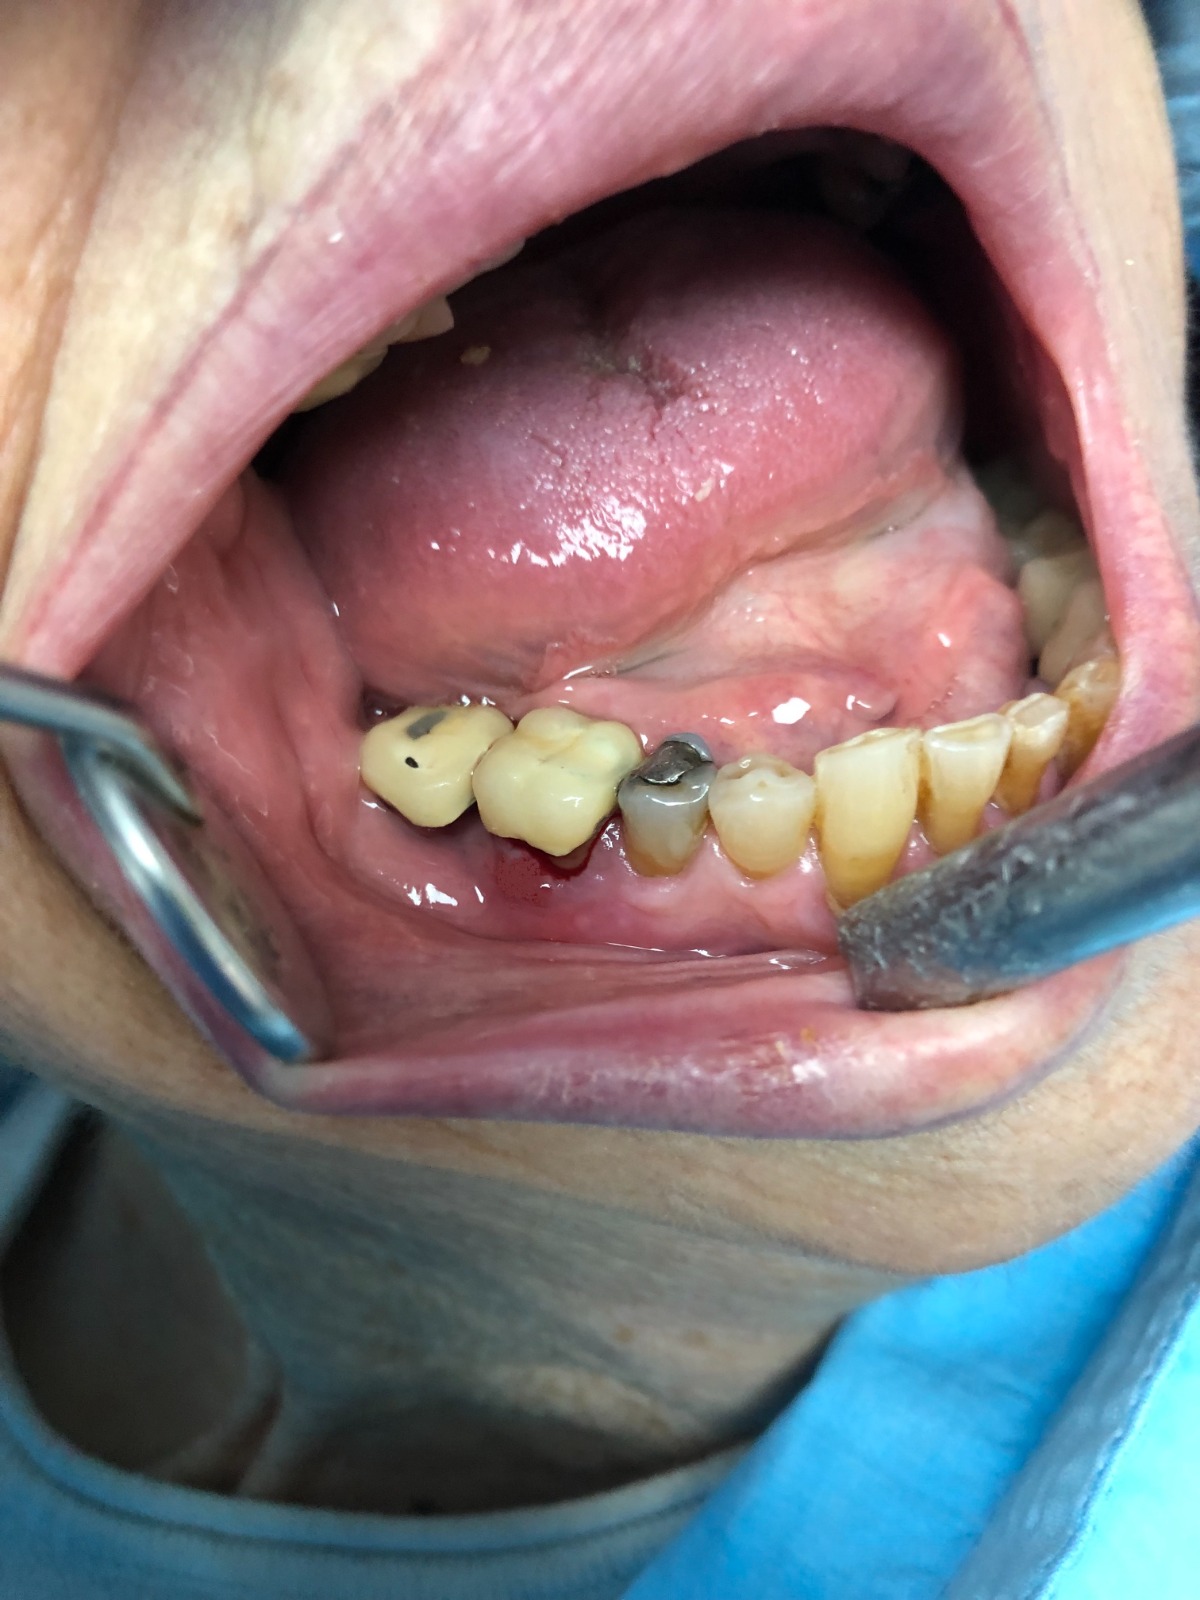

DOLOR EN PRÓTESIS SOBRE DIENTES NATURALES TALLADOS

Presentamos un nuevo caso en el que la paciente presenta un gran dolor en su prótesis antigua (15 años) sobre dientes naturales tallados en zona inferior de molares. Es una paciente muy bruxómana, se unieron dos molares tallados con dos coronas. En el caso que presentamos el molar anterior estaba endodonciado ya antes de colocar la prótesis fija, pero el molar distal no. Y éste era la causa del gran dolor. Esto es por haberse filtrado creando caries y destrucción dentaria que llegaba al nervio. En conclusión, produciendo una gran pulpitis.

Esto provocaba en la paciente un gran dolor, pero ella no contemplaba en ese momento la opción de levantar la prótesis para explorar las piezas que había debajo, poder visualizar la destrucción dental y rehacer todo con una prótesis nueva. Por tanto, para quitar el dolor normalmente habría que haber hecho las extracciones de los dos molares, lo cual sería muy invalidante. En la clínica decidimos hacer una endodoncia de la raíz distal del último molar a través de la prótesis por la zona oclusal, y hacer odontosecciones de las raíces lesionadas sin quitar la prótesis. Ésta va permanecer tal como estaba.